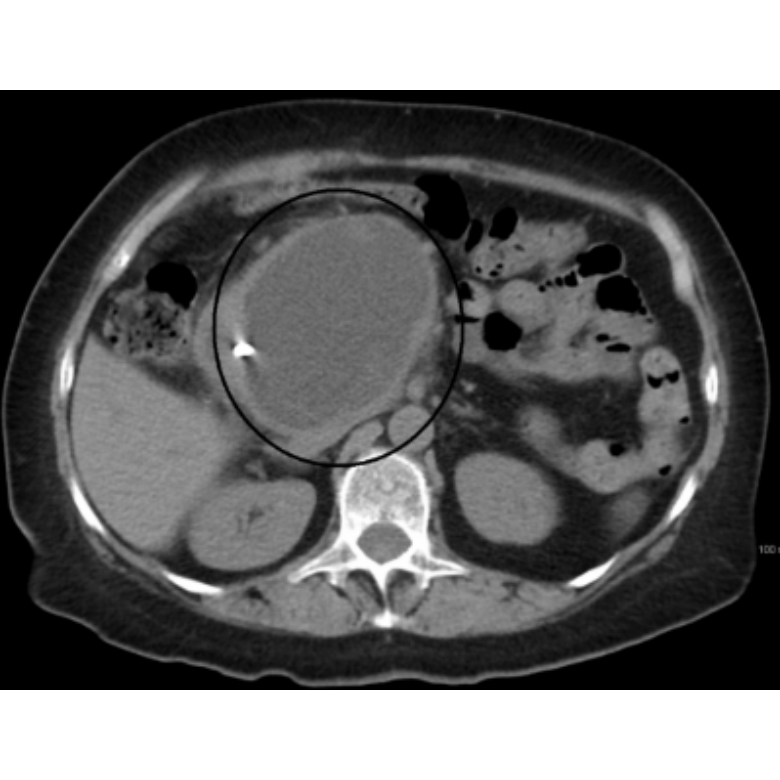

A pancreatic pseudocyst is a fluid-filled sac that forms in the abdomen, usually as a complication of pancreatitis, particularly chronic or severe acute pancreatitis. Unlike true cysts, pseudocysts do not have an epithelial lining; instead, they are surrounded by fibrous or granulation tissue. Pseudocysts develop when pancreatic enzymes and inflammatory fluids leak into the surrounding tissues, leading to the accumulation of fluid. They often contain pancreatic juice, blood, and necrotic tissue. Most pseudocysts form several weeks after the initial inflammation or pancreatic injury. Symptoms of pancreatic pseudocysts vary depending on their size and location. Small pseudocysts may be asymptomatic, while larger ones can cause abdominal pain, bloating, nausea, vomiting, early satiety, or a palpable abdominal mass. Complications include infection, rupture, bleeding, or compression of nearby organs such as the stomach or bile duct, leading to more severe clinical manifestations like jaundice or gastrointestinal obstruction. Diagnosis is typically made using imaging studies such as abdominal ultrasound, CT scan, or MRI. These tests help determine the size, location, and nature of the cystic lesion. Endoscopic ultrasound (EUS) can provide more detailed images and allow for aspiration of cyst contents for analysis. Management depends on the size, symptoms, and presence of complications. Asymptomatic pseudocysts smaller than 6 cm often resolve spontaneously. Symptomatic or enlarging pseudocysts, or those persisting beyond 6 weeks, may require drainage. This can be achieved through endoscopic, percutaneous, or surgical methods. Endoscopic drainage is often preferred due to its minimally invasive nature. In conclusion, pancreatic pseudocysts are important complications of pancreatitis that require careful evaluation. Timely diagnosis and appropriate management are essential to prevent serious outcomes and improve patient prognosis. Consult us today.👇 Contact Us📞 +91 7303055137 Email:care.cure.clinic.2020@gmail.com